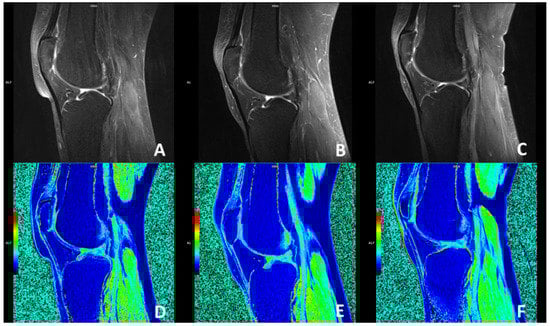

The magnetic resonance imaging using the dGEMRIC index showed no significant improvement in the glycosaminoglycan (GAG) composition of the cartilage in the knees treated with ACA-SVF and LP-PRP at 3- and 6-month follow-ups when compared to the baseline values for each of the analyzed compartments, including medial and lateral femur, medial and lateral tibia, trochlea, and medial and lateral patella (Figure 4).

Sagittal MRI magnetic resonance imaging (MRI) slices through the center of the knee accessing the patellofemoral joint osteoarthritic changes using fat-suppressed proton-density-weighted turbo spin-echo method at baseline (A), 3 months (B), and 6 months (C) follow-ups with corresponding delayed gadolinium-enhanced MRI of the cartilage (dGEMRIC) images (D–F). No changes were seen when dGEMRIC indices were calculated.